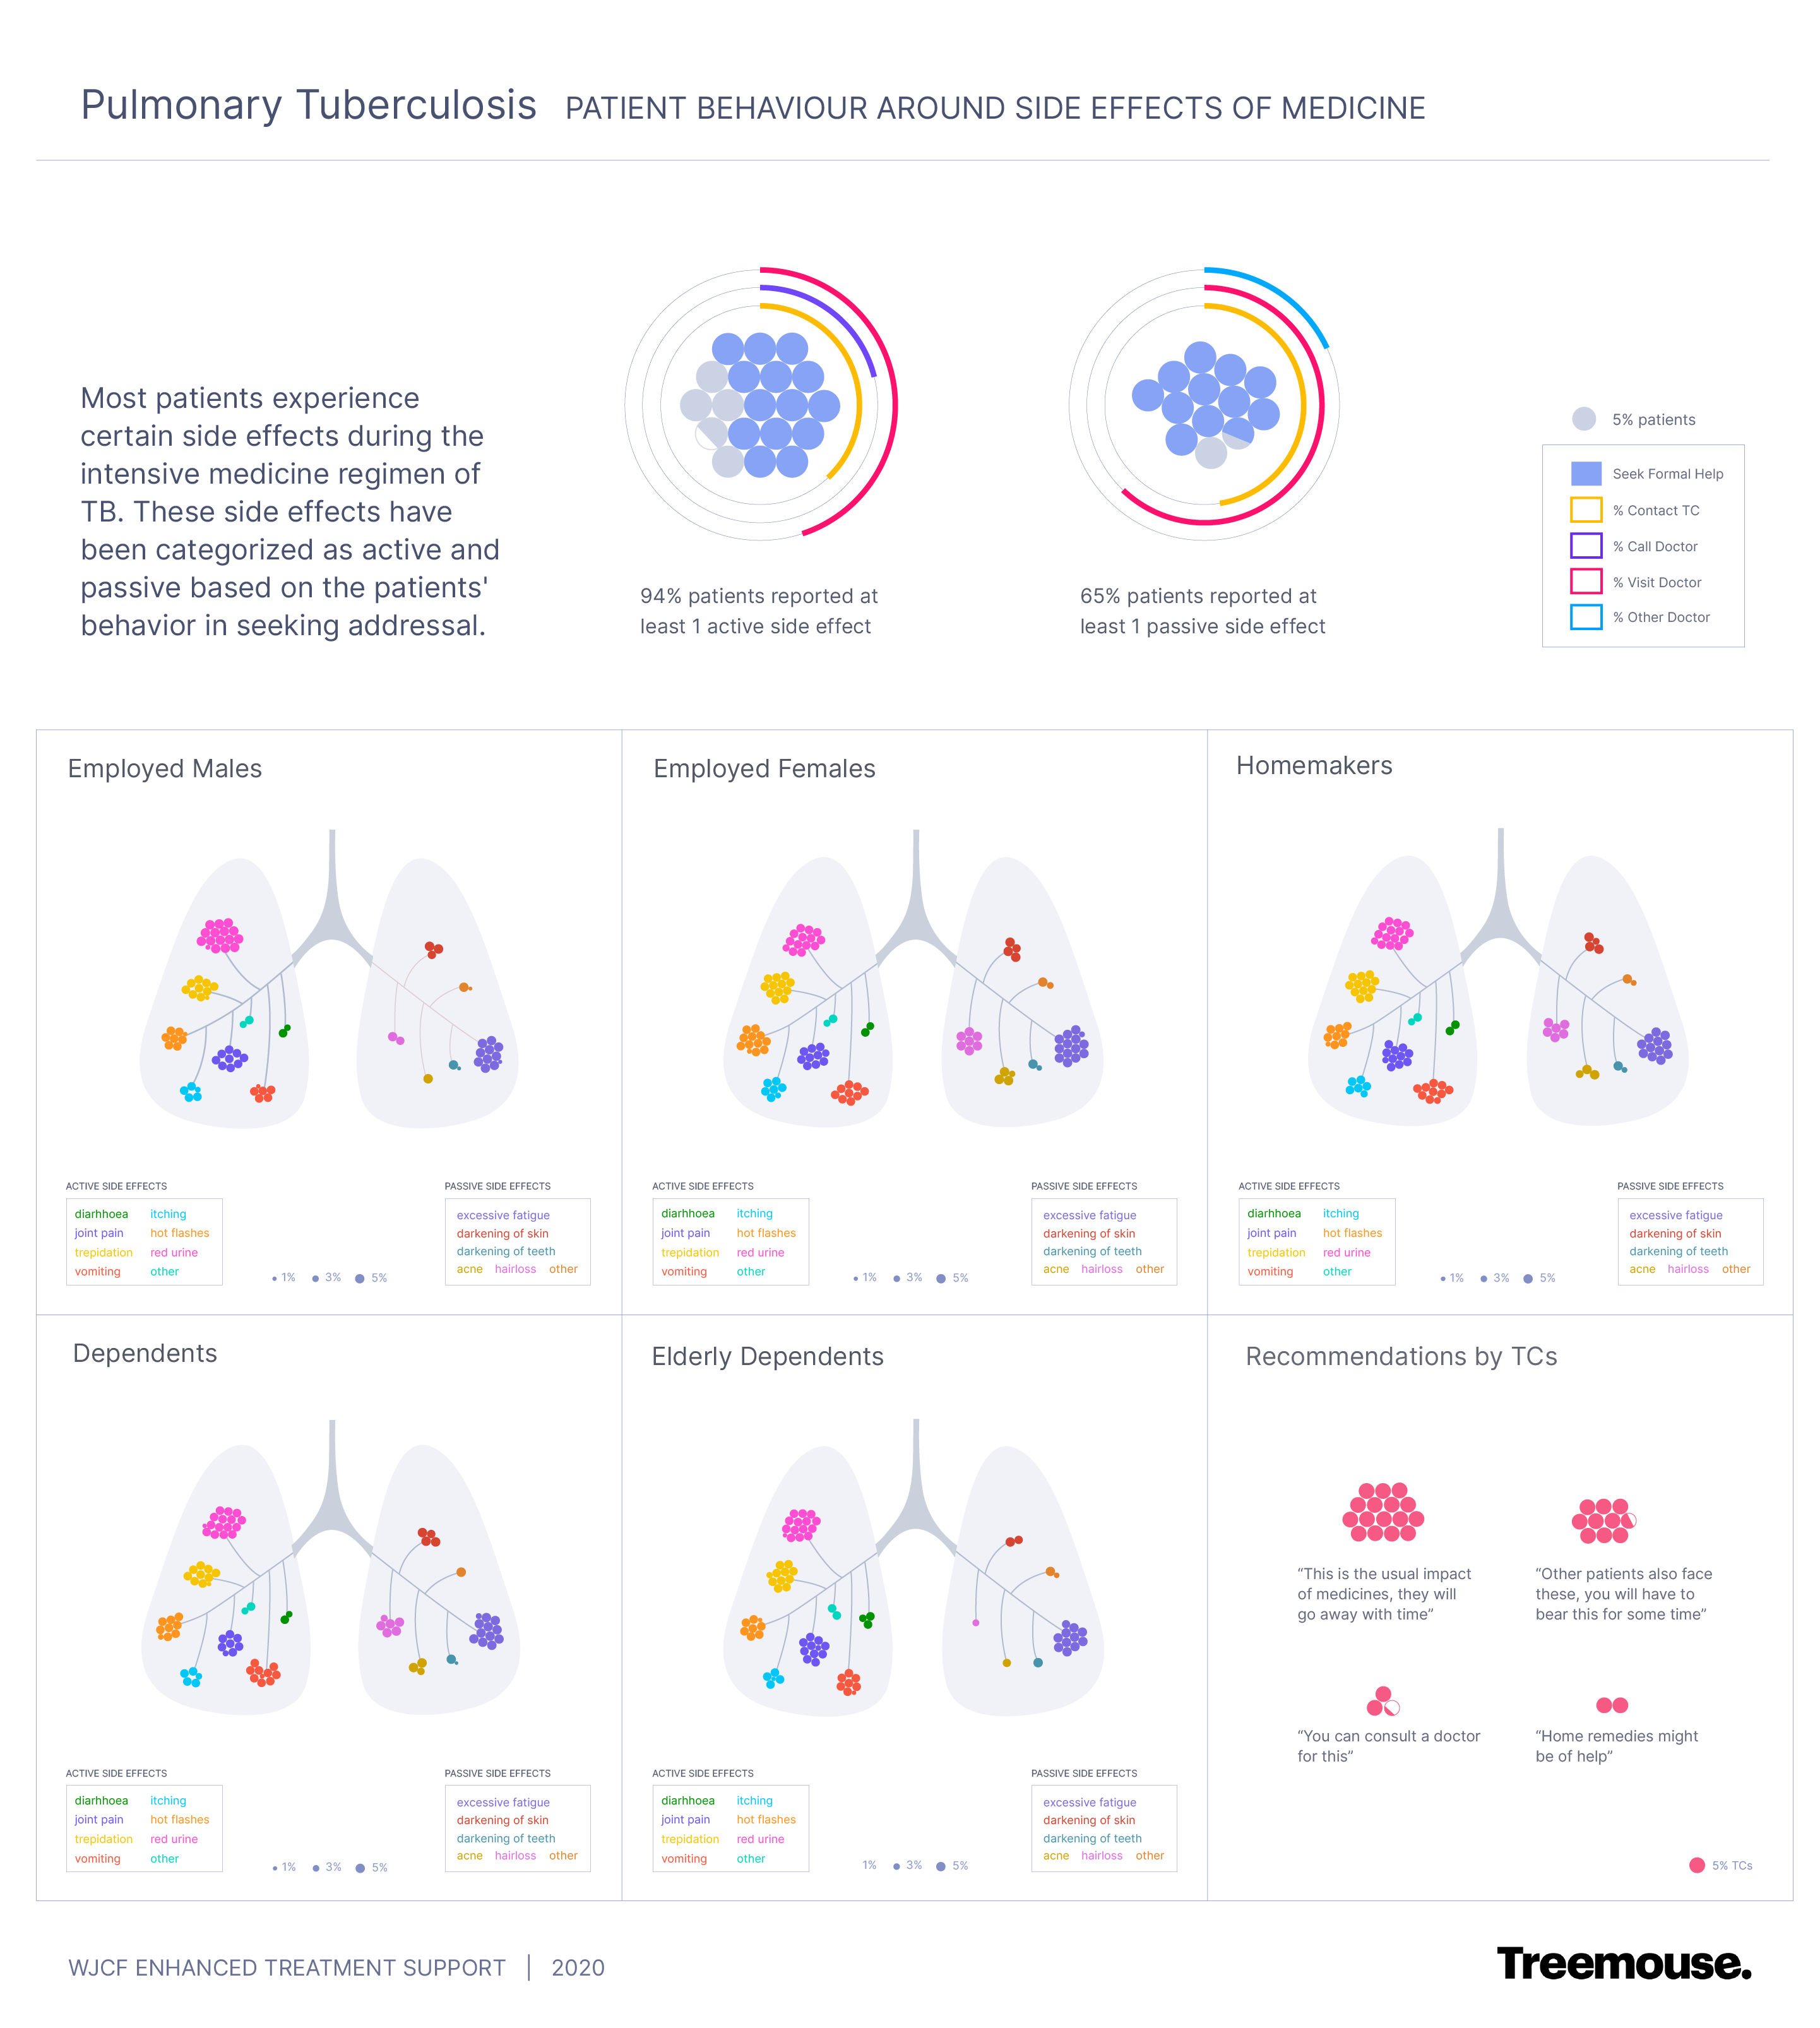

Sustenance is a higher priority for this segment of patients hence treatment related decisions are not static but continue to evolve over the long treatment duration, making it critical for the support system to evolve alongside. Our intensive study with patients and their immediate community uncovered these latent factors that dynamically influence their treatment adherence. We mapped this understanding over a deconstruction of JEET's systems and services to propose a patient-centric alignment of mandates. The findings were then validated at scale through a survey for a pan India rollout

We understood patient mindsets and motivations to identify socio-economic influences and instances where patients feel most vulnerable, including those that happen before diagnosis of TB and impact their adherence to the current treatment.

Patients react to TB diagnosis based on what would be impacted most in their lives, defining whether they will come back to the doctor to continue treatment, engage in doctor shopping or skip treatment altogether. This led us to define attitudinal patient profiles at that stage and ways to address their concern for increased uptake of treatment.

Patients' perspectives on TB are shaped by what they hear from immediate family and community, post diagnosis. This includes misinformation, further deepening the stigma against TB. It's therefore critical to provide clarity and confidence about their condition when diagnosed and equip them to counter instances of misinformation.

Earlier, the change of treatment phase was considered to be a point of probable dropoff with JEET deploying additional support around it to move patients out of their inertia. Our findings reflected otherwise. Patients considered the change as an accomplishment and stayed in treatment with the inertia actually setting in 3-4 weeks later.